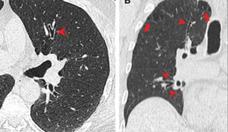

Marcos de Abreu, pneumologista da Funda��o S�o Francisco Xavier, ressalta que uma das principais doen�as associadas ao tabagismo � a pulmonar obstrutiva cr�nica (DPOC)